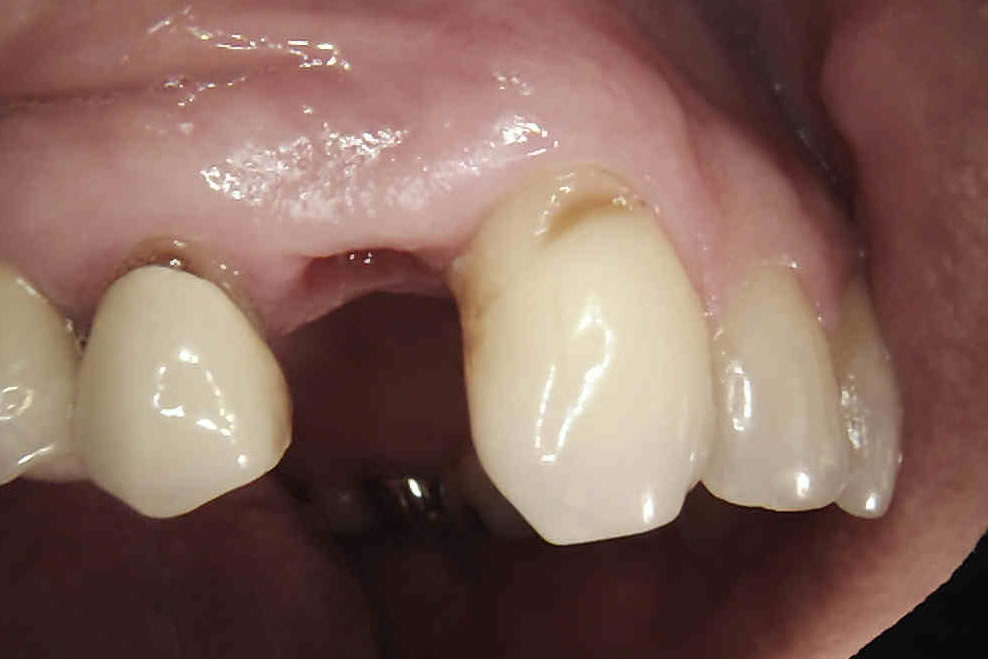

IMPLANTS FOR SINGLE & MULTIPLE MISSING TEETH

Dental implants are the best-known treatment to replace single or multiple missing teeth because they feel and behave just like natural teeth. After a while you won’t be able to tell the difference – even forgetting that they are there.

The procedure to place implants and replace a missing tooth or multiple teeth is straightforward as there is little need to treat surrounding teeth. Once a crown is placed over the implant it will appear indistinguishable from the natural teeth.